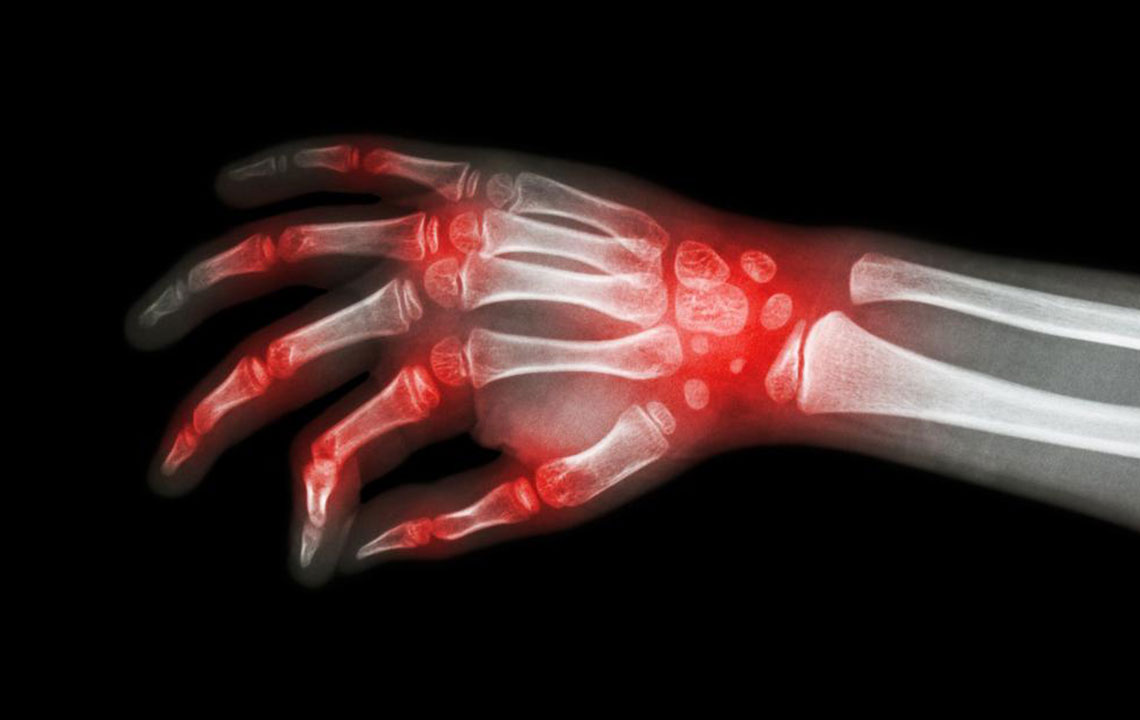

Lupus and rheumatoid arthritis are both autoimmune conditions that are often confused to be the same. The fact that these – rheumatoid arthritis, lupus are autoimmune diseases makes their symptoms similar too. Auto immune diseases are typically those conditions where the immune system of the body attacks healthy cells, causing inflammation, swelling, and pain in the affected areas.